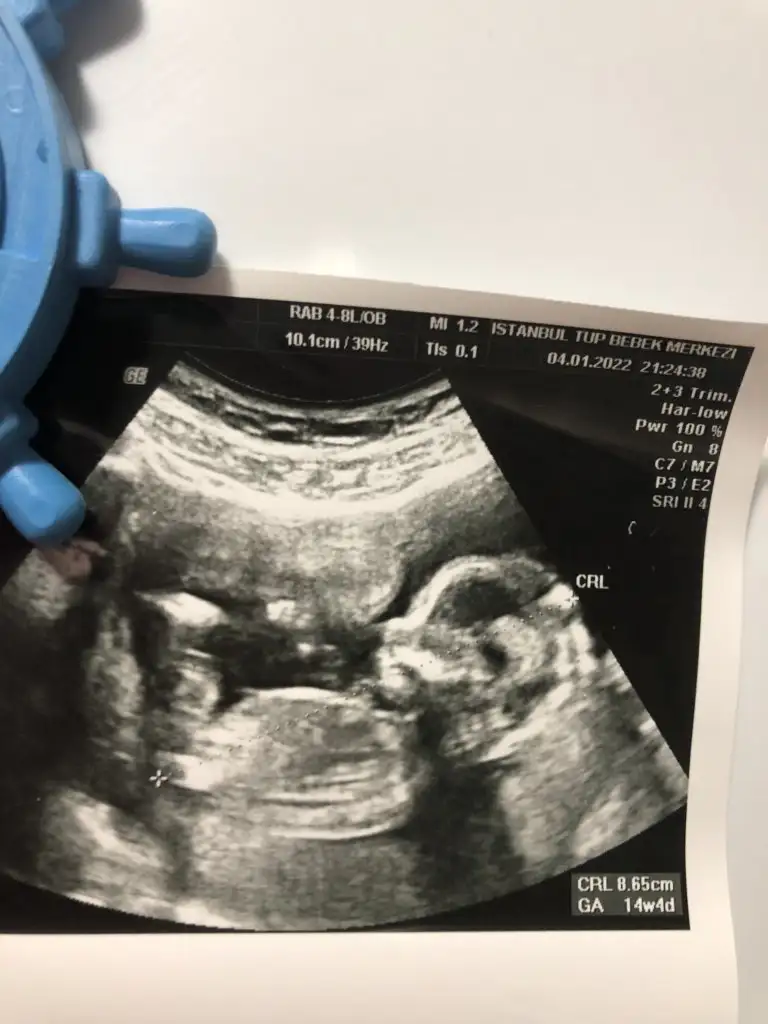

CRL boyu canım. 8,65cm henüz. 🤗

Crl yazan boyu 8.65 cm canım

14 hafta 4 günlük